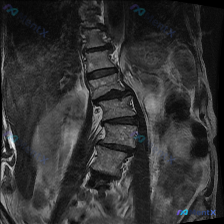

今天看到这个腰椎MRI轴位片的读片需求,整理了完整的影像分析和鉴别思路,分享给大家。 病例影像基本信息 这是一张腰椎MRI T2加权轴位影像,定位在腰椎下段椎间盘层面,大概率是L4/5或L5/S1,具体需要矢状位确认。 影像可见的基本结构和异常: 1. 椎体结构清晰,椎间盘髓核信号明显减低,符合椎间...

整理到一张腰椎MRI的冠状位T1WI图像,先不说结论,大家第一眼会怎么看? 目前能看到的影像表现: - 腰椎明显向右侧凸,有椎体旋转和倾斜 - 两侧椎间隙高度不均匀,部分变窄 - 多个椎间盘信号降低 - 椎体骨髓信号基本是弥漫中等偏高,没看到明确的局灶骨质破坏或大肿块 - 两侧腰大肌形态不对称 这份...

最近看到一份腰椎MRI的描述,觉得挺有警示意义,整理一下思路和大家讨论。 病例核心影像信息 - 关键征象:L4-5椎间盘水平,下缘可见中央及右侧旁中央高信号病灶,且与椎间盘直接相通 - 其他影像表现:L4-5椎间盘后缘弥漫性、对称性信号降低(退变脱水);椎间盘后缘广泛性膨出伴局灶性后正中偏右侧突出;...